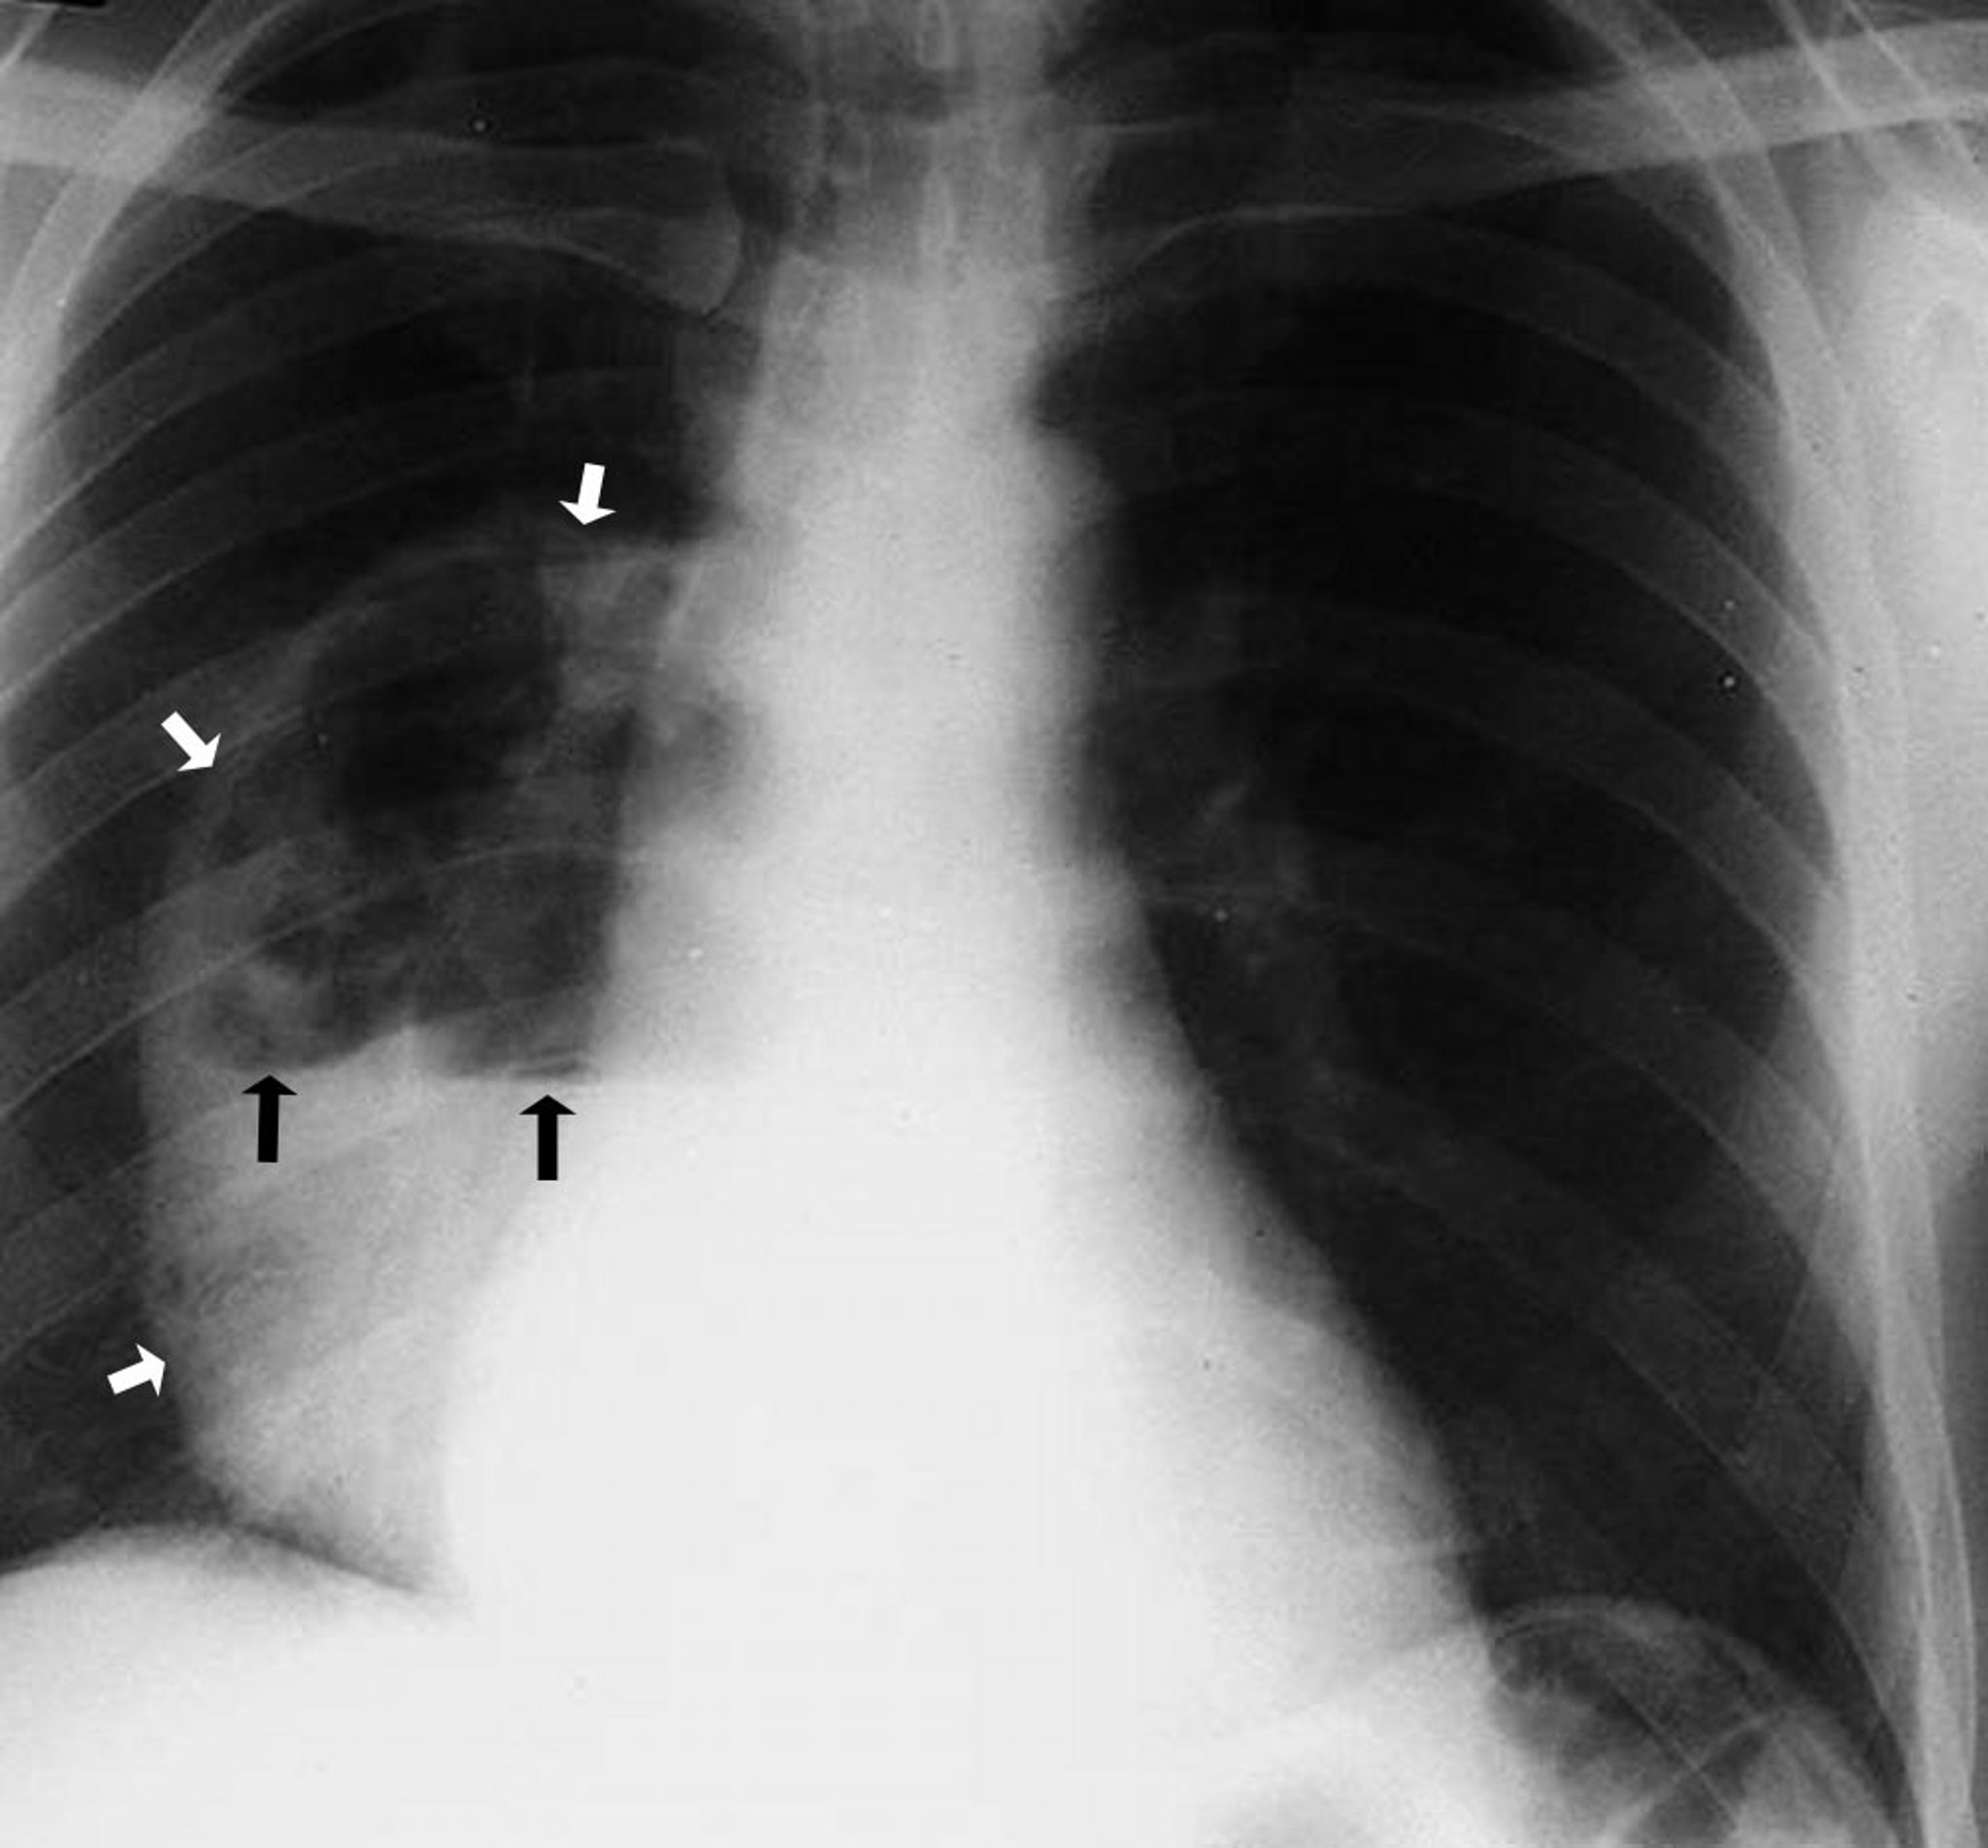

Ascesso polmonare (radiografia)

Questa foto mostra un grande ascesso del lobo inferiore destro che mostra una cavità che contiene un livello idroaereo. Le frecce bianche indicano il bordo dell'ascesso, mostrando le pareti separate dal parenchima polmonare. Le frecce nere delimitano il livello in cui l'aria sopra e il fluido sotto si incontrano.